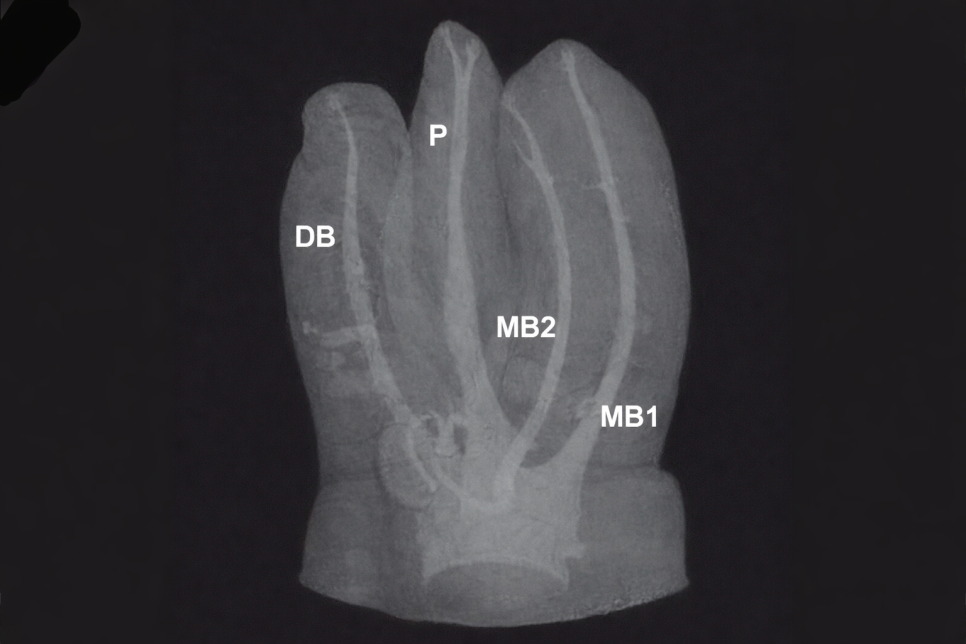

윗쪽 첫 번째 큰 어금니의 뿌리는

통상적으로 3개입니다.

그런데 간혹 4개인 경우가 있는데요.

이런 케이스는 근심협측치근이라 불리는 부분이

두 갈래로 갈라져 마곡동 치과

사진처럼 MB2 근관이 관찰됩니다.

관찰이 어렵기 때문에 간혹 놓치는 경우도 있는데

그럼 MB2가 재감염의 경로가 될 수 있습니다.

그런데 이 근관의 문제는 관찰이

어렵다는 점에서 끝나지 않습니다.

발견이 어렵다는 점과 더불어

석회화되어 입구를 찾기도 힘듭니다.

그래서 기구가 발견했다 하더라도

입구로 기구가 들어가기 어려워

치료가 길어질 수도 있죠.

또한 근심협측치근이 두 갈래로 나눠지면

각각 MB1/MB2라 부르게 되는데,

한쪽은 일반적인 굵기를 가지고 있으나

MB2는 아주 얇습니다.

그래서 잘 보이지 않고 마곡동 치과 사진처럼

입구를 찾는 게 어려운 것이죠.